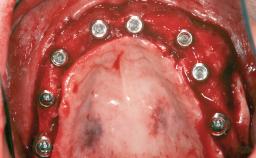

A 45-year-old woman with a completely edentulous maxilla was referred to evaluate the possibility of rehabilitation with an implant-supported prosthesis. This patient was healthy and a non-smoker. She had been wearing a maxillary complete denture opposing a natural mandibular dentition since her twenties. This situation had resulted in progressive resorption of the alveolar ridge, repeatedly creating a need for relining the denture. Twenty years later, despite multiple adaptations and the use of “glues” the denture was unstable and causing the patient psychological and functional discomfort.

| # of Implants | 8 |

| Bone Augmentation | Horizontal|Sinus Floor Elevation|Staged|Vertical |

| Augmentation Materials | Autogenous chips|Autogenous block(s) |